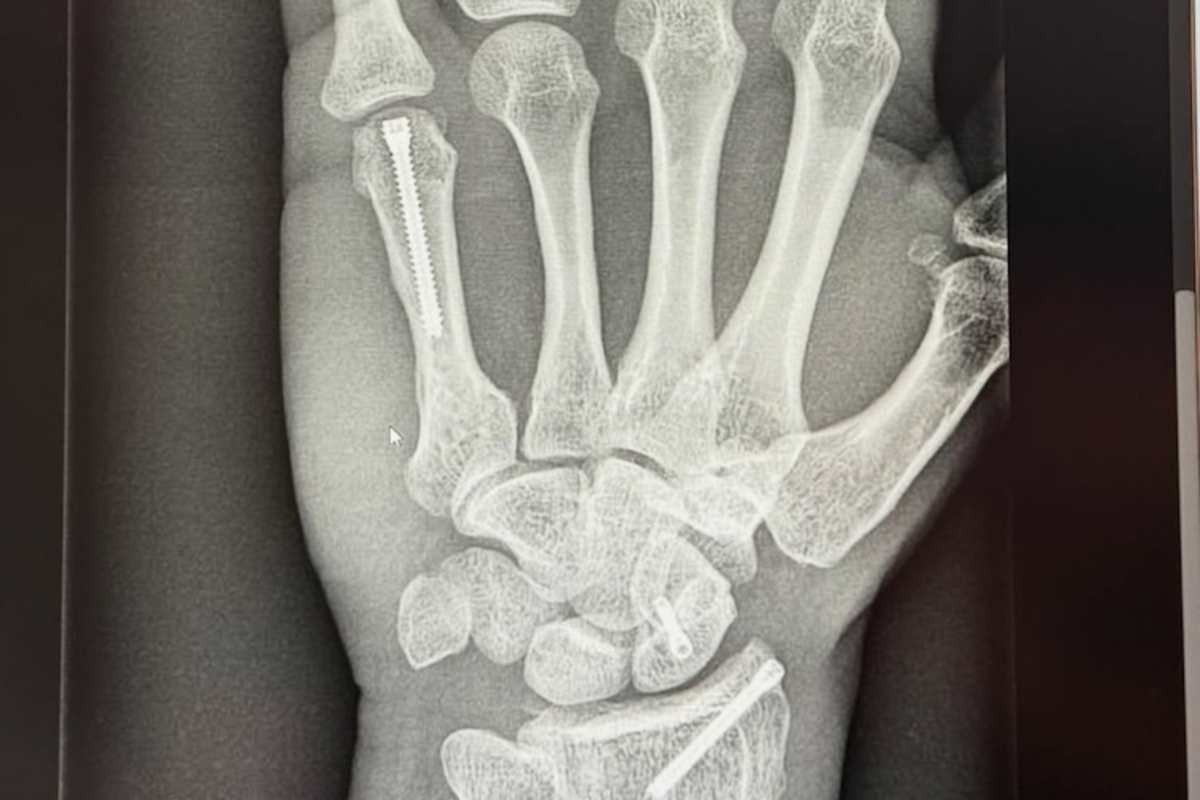

Viel schlimmer hätte es nicht kommen können. Bekanntermaßen hatte es den MotoGP-Weltmeister beim Testauftakt 2024 nach gerade einmal vier Runden per Highsider hart erwischt. Mit Brüchen in der rechten Hand sowie im linken Fuß war Jorge Martin schnell auf dem Rückweg und bereits auf dem Operationstisch in Barcelona, als in Malaysia um die letzten Test-Bestzeiten gerauft wurde. Der in Rennfahrerkreisen bestens bekannte Chirurg Dr. Xavier Mir leitete die Eingriffe.

Aufgrund der mehrfachen Frakturen stand schnell fest, dass die Startnummer 1 den Test in Thailand auslassen muss. Sowohl bei Aprilia Racing als auch beim verletzten Champion besteht 10 Tage vor WM-Auftakt in Buriram aber kein Zweifel an einem Comeback beim Thailand-GP. Erstmals seit seinem Rücktransport in seine Wahlheimat nach Andorra veröffentlichte der aus Madrid stammende Pilot jetzt Bilder seiner Rehabilitation. Die findet nach wie vor in Andorra statt und besteht neben einer regelmäßigen medizinischen Kontrolle auch bereits wieder aus Konditionstraining. Auch dank seiner engen Verbindung zu Aleix Espargaro zählt Jorge Martin zu den austrainiertesten Athleten der Königsklasse. Auch im Umgang mit Verletzungen ist der jetzige Aprilia-Werksfahrer erfahren. Den bis dato schwersten Rückschlag hatte Martin während seiner MotoGP-Rookie-Saison im April 2021 zu verkraften. Bei einem gewaltigen Abflug in Portimao brach sich Pramac-Pilot insgesamt acht Knochen, unter anderem in beiden Händen sowie im rechten Fuß.